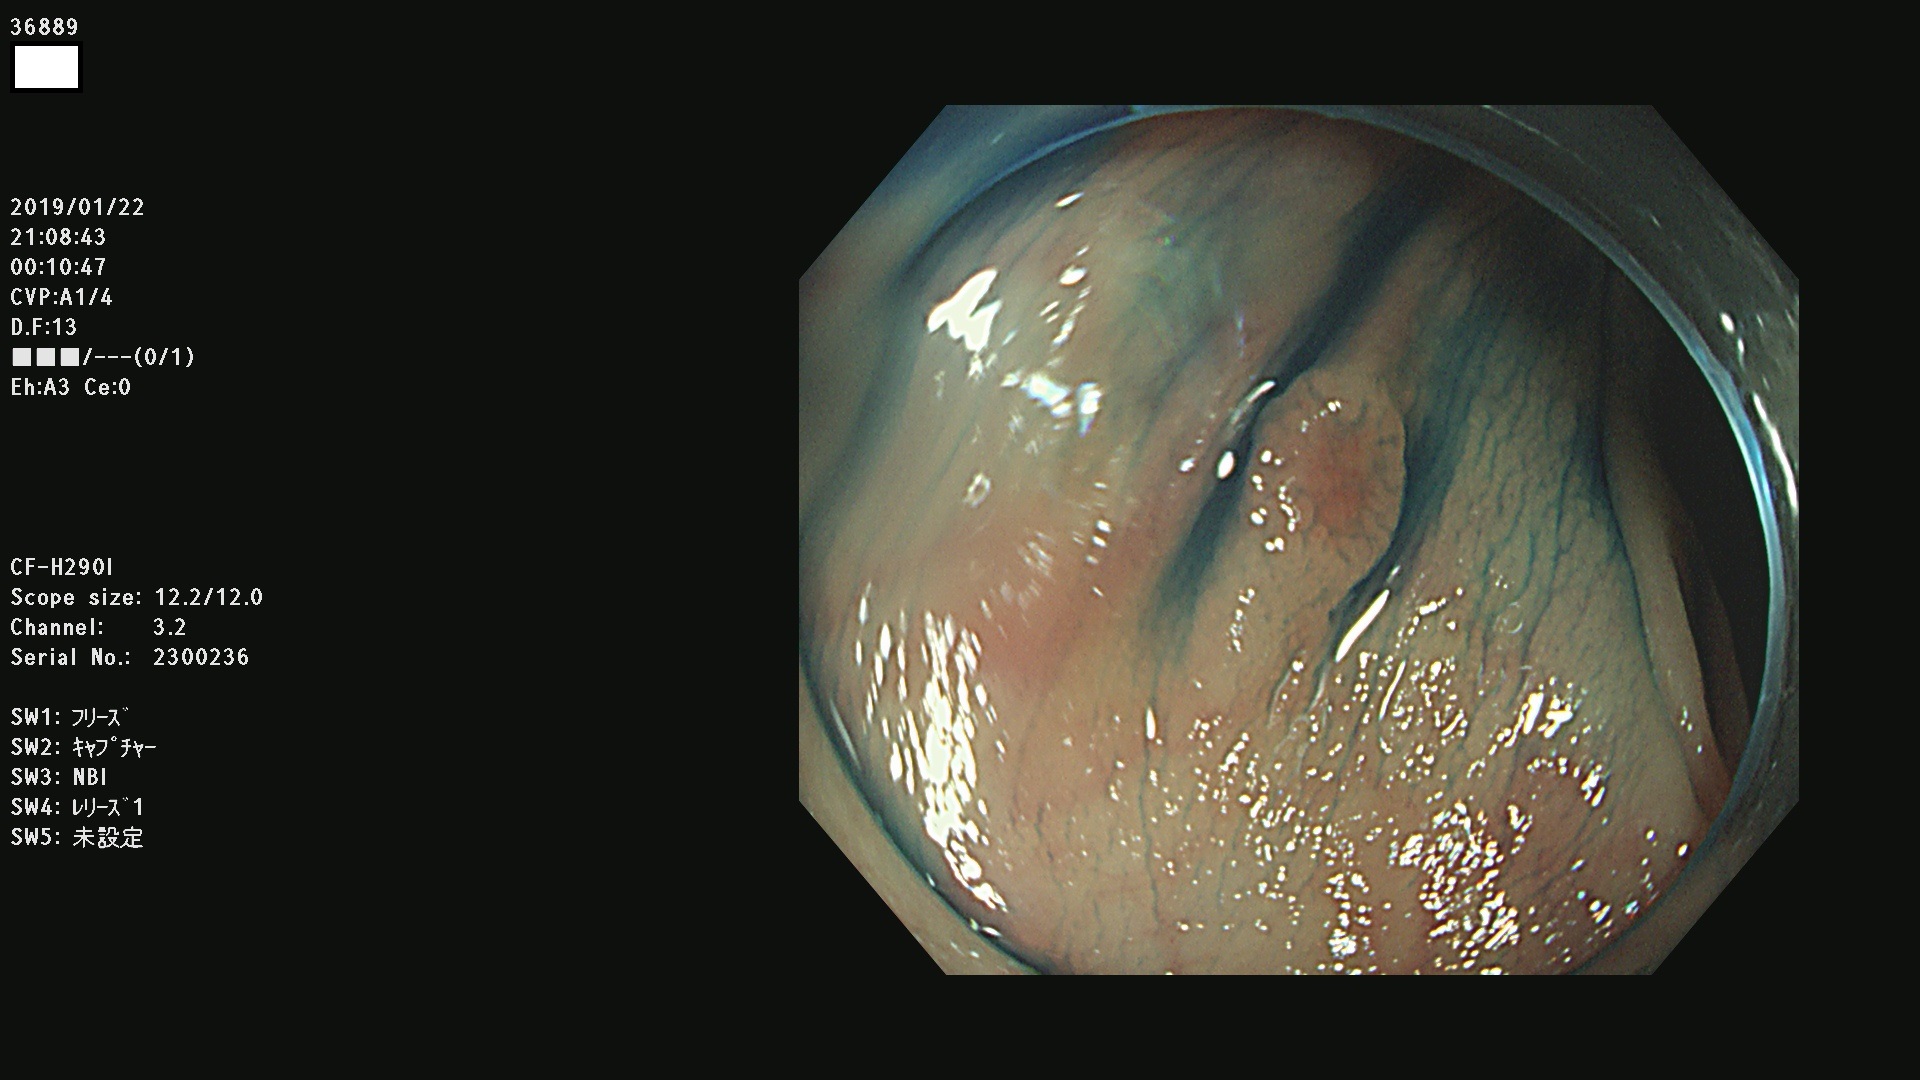

36804 36806 36807 36808 36809 36810 36811 36813 36815 36816 36817 36818 36820 36821 36822 36824 36825 36826 36828 36829 36830 36831 36832 36833 36834 36835 36837 36840 36841 36842 36845 36846 36848 36849 36851 36852 36853 36854 36855 36857 36859 36860 36861 36862(SSAPのみ) 36863 36864 36866 36868 36869 36870 36873 36875 36877 36878 36879 36881 36882 36883 36884 36885 36886 36887 36888 36889 36891 36892 36893 36894 36895 36896 36897 36898 36899

発見困難で危険性の高い平坦型病変(上記100名より抽出)